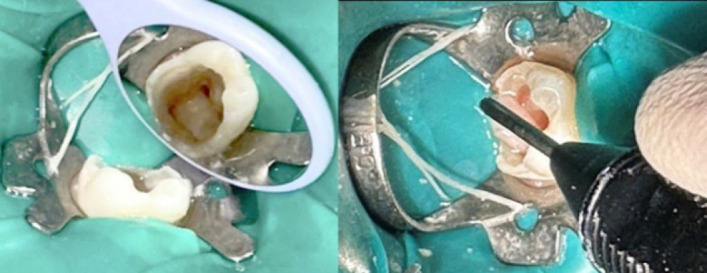

Regenerative endodontic procedures (REPs) have emerged as a biologically driven approach for managing immature teeth with necrotic pulp and open apices, providing an alternative to traditional apexification techniques. This case report describes the successful treatment of a three-rooted immature mandibular first molar with necrotic pulp and chronic apical periodontitis in a 9-year-old patient using REPs. The treatment followed the guidelines set by the American Association of Endodontists and utilized a two-visit protocol. Concentrated growth factor (CGF) was employed as a biological scaffold in the root canals, while calcium-enriched mixture (CEM) cement was used for the coronal seal. Radiographic evaluations conducted at 6, 12, and 15 months revealed progressive periapical healing, significant root elongation, increased thickness of the root walls, and partial apical closure. Clinically, the patient remained asymptomatic during all follow-ups. This case highlights the potential of CGF and CEM cement-enhanced REPs to promote continued root development and achieve predictable outcomes in immature teeth with necrotic pulps, offering a biologically based alternative to conventional apexification.